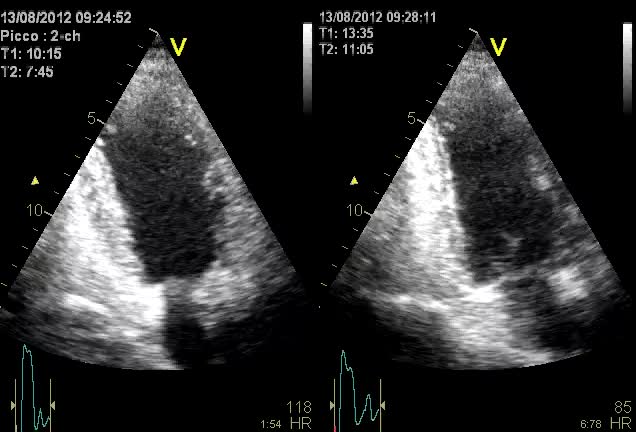

Alterazioni cinetica

Autore:

Anna Maltagliati